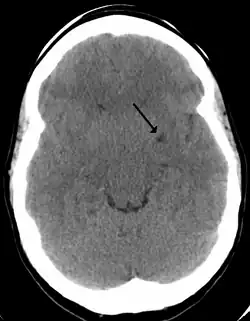

Axial fat-suppressed T2-weighted MRI image in the same patient as above demonstrating extensive dilated Type 2 perivascular spaces in the right hemisphere